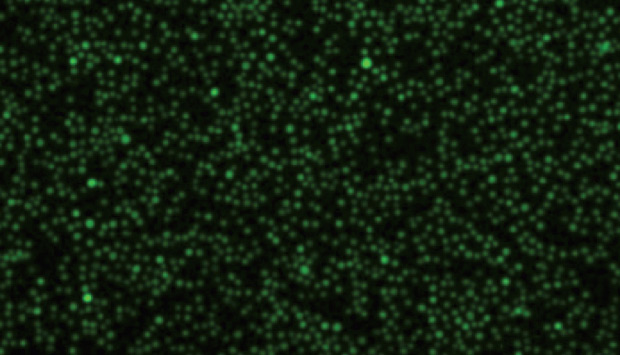

Fluorescence microscopy image showing green fluorescent protein expression in sonoporated human B cells.

In one cell line, for example, the researchers achieved around 43 per cent transfection efficiency through sonoporation, compared to just 3 per cent with a conventional transfection method called lipofection (see image). Through further selection techniques, the researchers enriched the population of transfected B cells to more than 70 per cent. They achieved similarly impressive results with the two other B cell lines.